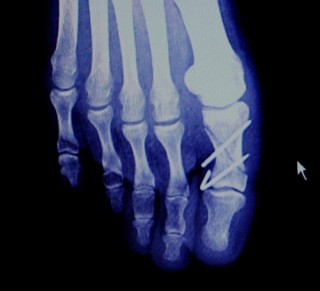

手術(2006年11月17日)の次の日。

折れた部分に2本、ピンを打ち込みました。

ピンの様子。2本打ち込まれています。